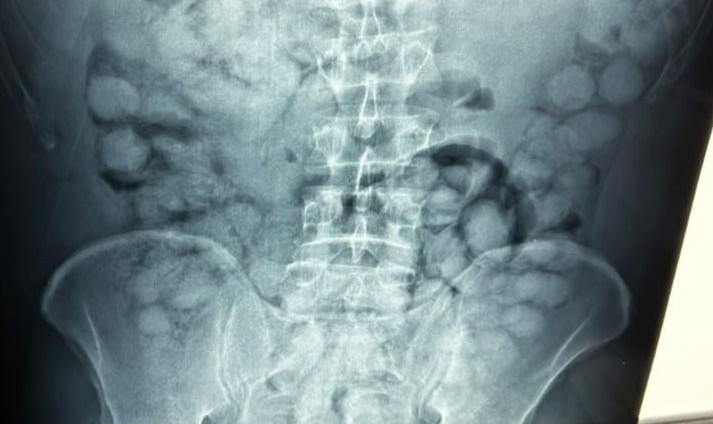

Ο άνδρας, που ταξίδευε από Βραζιλία μέσω Γαλλίας, είχε καταπιεί 100 συσκευασίες κοκαΐνης. Η κάθε συσκευασία ήταν 10 γραμμαρίων και καθαρότητας 90%.